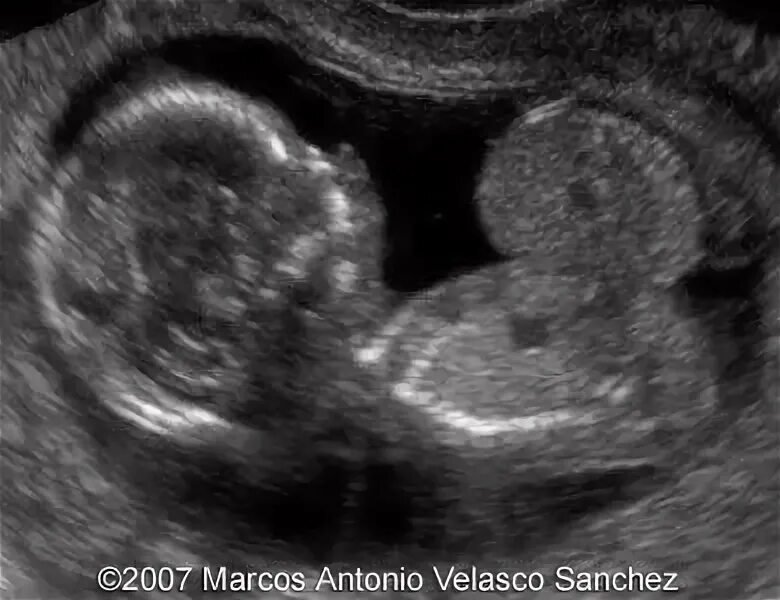

Узи шип